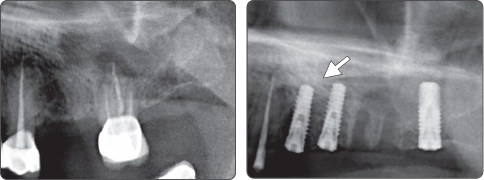

▶ Immediate Implantation and Sinus Lift Technique with Tap Drill (Ø4.0 Fixture)